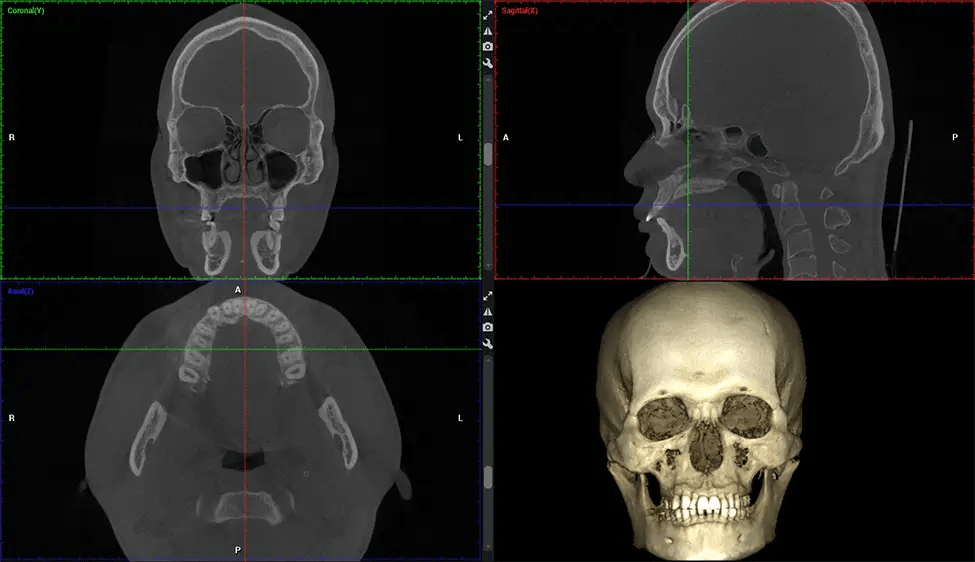

Cone Beam Computed Tomography (CBCT) is an advanced imaging technique used in dentistry and maxillofacial surgery to obtain detailed 3D images of the oral and maxillofacial structures. At Dr G Dental Studio, our CBCT scanners utilize a cone-shaped X-ray beam and a specialized detector to capture images from different angles. A computer then combines these images to create a 3D representation of the patient’s oral anatomy.

This 3D scan, called cone beam computed tomography, gives your dentist a more complete image of your oral anatomy and disease processes than a traditional X-ray. Unlike conventional X-rays, which capture a 2D image of your mouth from various angles, a 3D scan takes multiple digital X-rays for one image. It provides a complete view of your jaw, teeth, nerves, and soft tissues. This enhanced view allows dentists to detect minor issues not visible in traditional 2D scans, such as impacted wisdom teeth or bone fractures in the sinus cavity.

There are many benefits to using CBCT technology, especially compared to the traditional 2D X-ray format. One of the most significant advantages of CBCT scans is that they provide much more information than traditional X-rays. A scan lets your dentist see images from all angles of your jaw and mouth, including your sinuses, nasal cavity, cheekbones, and other surrounding areas. This added information helps your dentist craft a comprehensive treatment plan that addresses all aspects of your oral health.

Another significant benefit is that 3D imaging provides more precise images of your bone structure. These images are more detailed, providing you with a more accurate diagnosis. An accurate diagnosis means better treatment for you.

The patient is first positioned in the CBCT scanner, which typically consists of a rotating arm that houses the X-ray source and a detector. The patient’s head is immobilized to ensure accurate image capture. The X-ray source and detector rotate around the patient’s head, capturing various X-ray images from multiple angles. As the X-ray source rotates, it emits the cone-shaped X-ray beam towards the detector. The detector captures the X-ray images, which are then processed by the CBCT software.

After the scanning process, the captured X-ray images are processed by the CBCT software, which applies algorithms to reconstruct a detailed 3D image of the scanned area. The software compiles these individual X-ray images and creates a digital 3D representation of the patient’s anatomy. The reconstructed 3D CBCT image can be viewed and analyzed by the dentist or radiologist. This image can be manipulated, rotated, and zoomed in or out to examine specific structures and evaluate the patient’s condition.